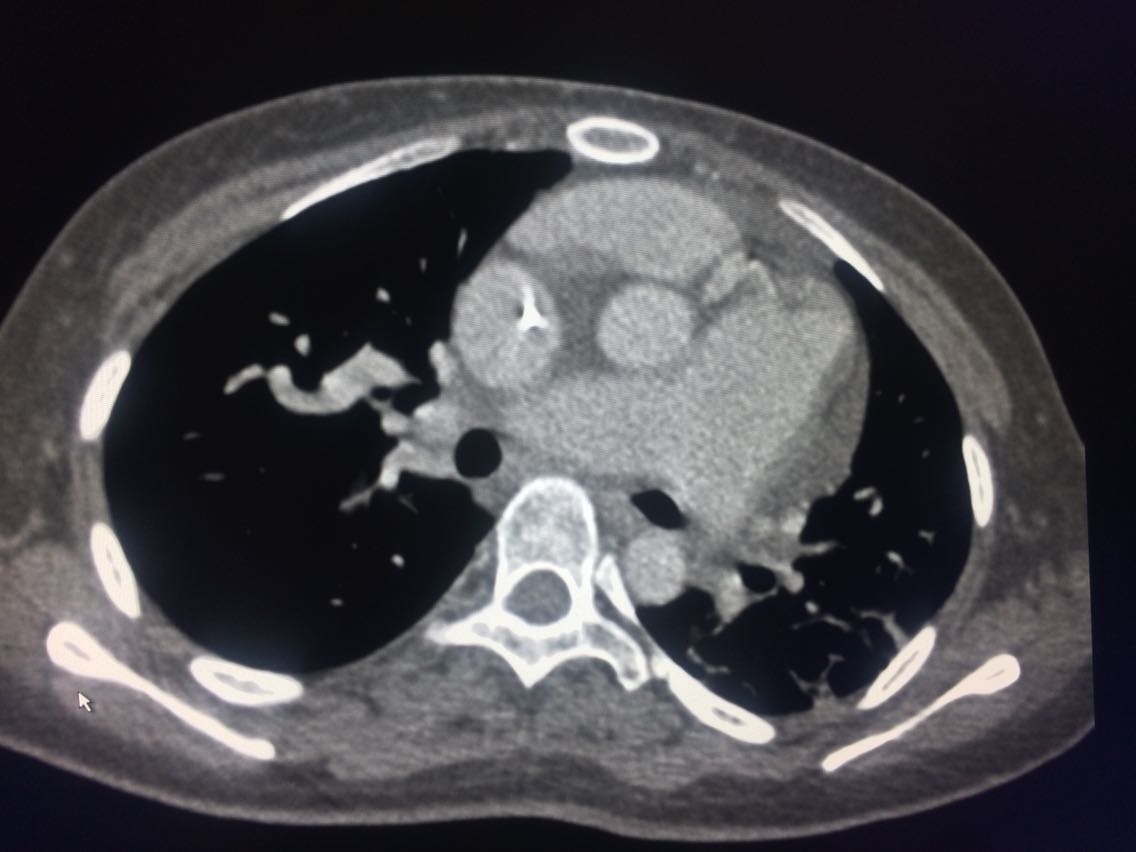

诊断,肺动脉高压。 鉴别诊断,肺动脉栓塞。 影像诊断,肺动脉高压,肺门区出现残根征,肺动脉扩张,肺动脉段膨隆,心影增大。CTA见迂曲增宽的肺动脉。 肺栓塞,影像可见典型充型缺损影,伴随肺纹理的减少。 治疗以对症处理为主,病人病史14年。 讨论诊断和鉴别诊断? 随访,症状好转。